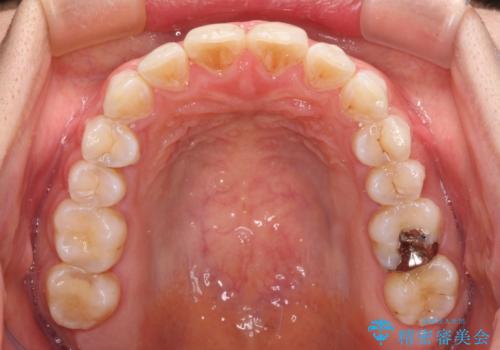

前歯の捻れを改善 インビザラインによる矯正治療

- 前歯の翼状捻転を気にして来院された患者様です。

全体的に叢生は軽度であったため、インビザラインにて矯正治療を行うこととしました。

前歯の幅の大きさも気になっていたため、IPRにより叢生を解消するとともに、歯の大きさも改善しました。